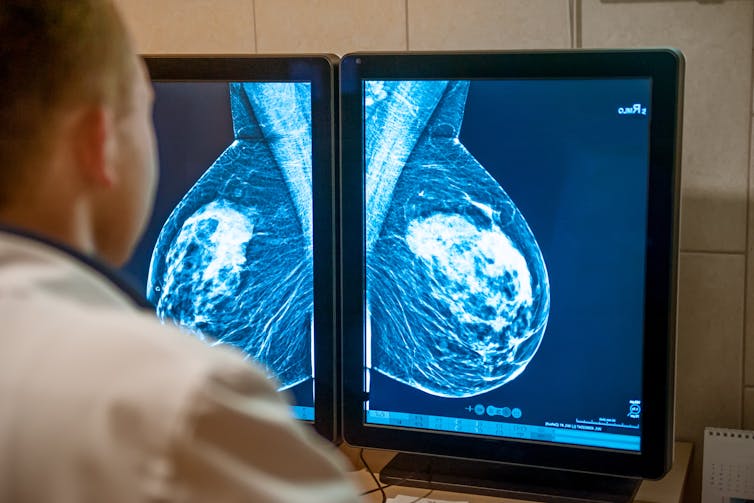

Despite rapidly rising rates of breast cancer in younger women and overwhelming evidence supporting the efficacy and cost-effectiveness of screening, the Canadian Task Force on Preventive Health Care has recommended against systematic screening for women between the ages of 40 and 49.

The decision to not endorse breast cancer screening for young women is perplexing and dangerous, given that early detection is critical in the fight against breast cancer.

The Task Force disproportionately focuses on the potential harms of screening, such as over-diagnosis (the diagnosis of a cancer that would never have caused problems for an individual in their lifetime) and anxiety around imaging callbacks, while minimizing the undeniable benefits of saving lives and reducing suffering through early detection.

While randomized controlled trials (RCTs) are the gold standard for guideline formulation, the reliance of the Task Force on 30- to 60-year-old outdated RCTs fails to account for modern diagnostic and treatment advancements. The guideline process was paused in the fall, with experts demanding that only evidence from after 2000 be considered. However, this advice was ignored, and the Task Force continued to disproportionately prioritize aged RCTs and undervalue recent observational trials, which better align with present screening and treatment norms.

This diminishes the perceived benefit of screening, as the mortality benefit of screening in RCTs is 15 per cent, compared to 53 per cent in observational trials. The Task Force also tells only part of the story of the benefits of screening by framing its advantages within a limited time span (10 years from entry into screening), and not manifesting the accrued benefits over an individual’s entire lifetime.